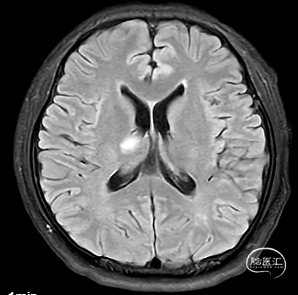

右侧中脑-丘脑可见新发脑梗塞:

颅内外血管未见明显狭窄。

CT(CTA)检查提示:右颈内动脉C7段大小约3.6×3.8×3.6mm及基底动脉远端动脉瘤形成大小约9.7×7.6×9.3mm。